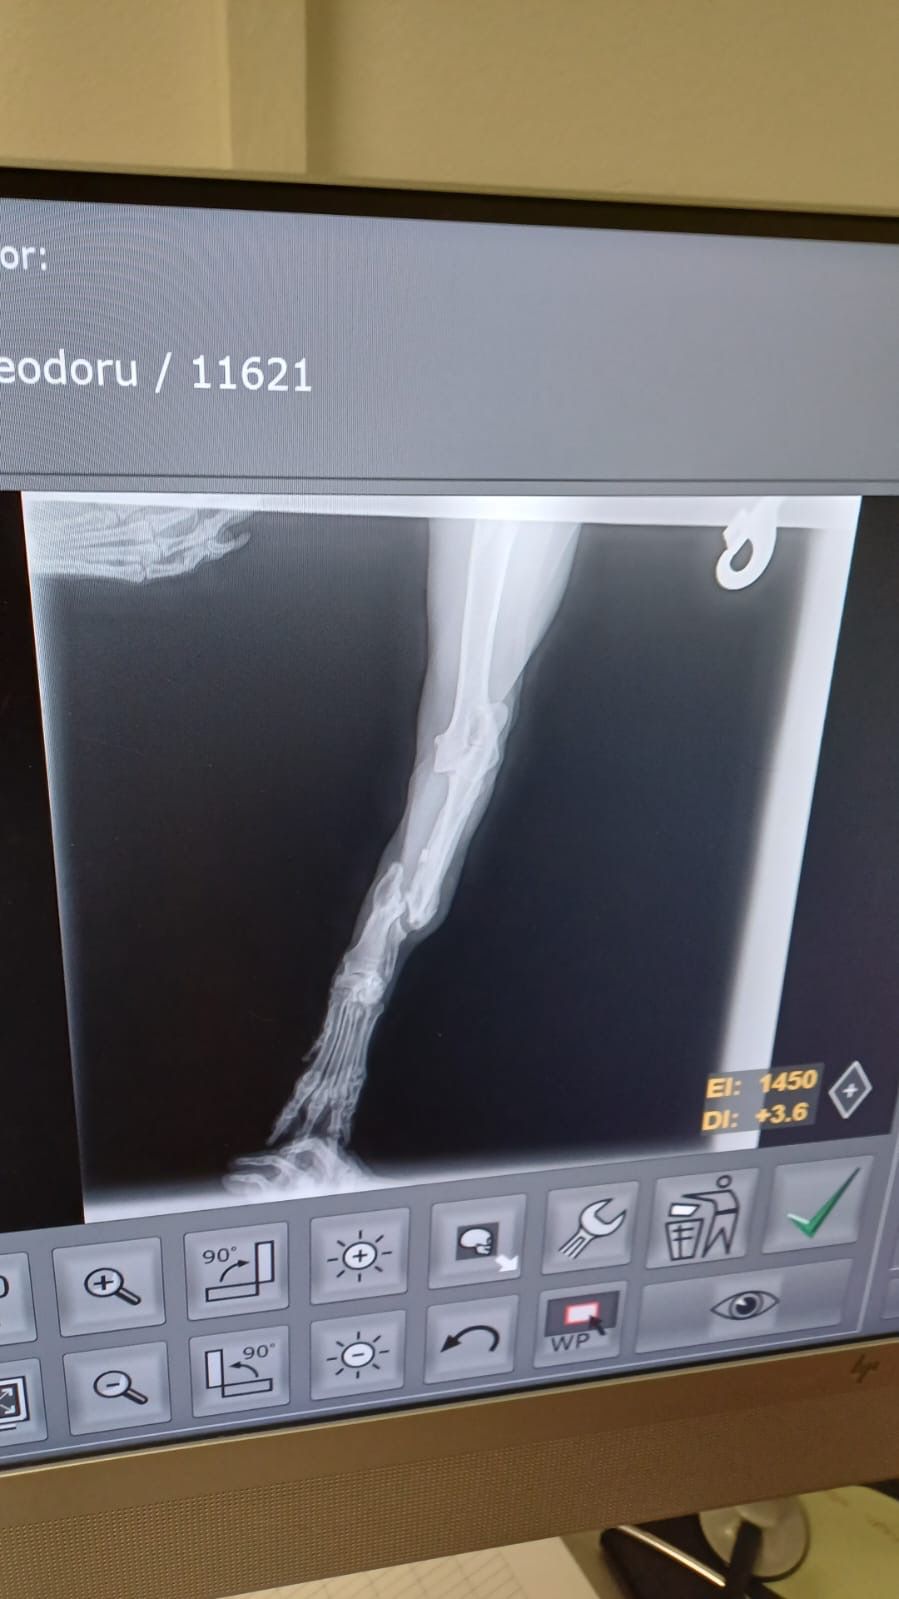

Leider stimmt etwas mit seiner linken Vorderpforte nicht, mit dieser humpelt er und wenn er sie aufsetzt, ist sie völlig durchtrittig und wirkt sehr instabil. Möglicherweise liegt hier eine (ältere) Verletzung vor.

linkes Vorderbein wurde amputiert

| zur Besonderheit: | linkes Vorderbein amputiert |